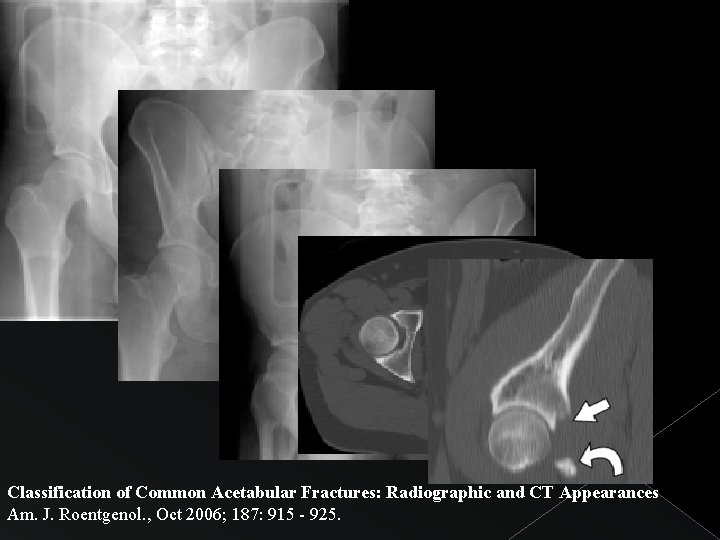

FRACTURA EN “T” Fractura transversa acetabular + Extensión hacia anillo obturador Disrupción de ilioisquiática. líneas iliopectínea e identificar componente transverso de la fractura Importante La copa acetabular está inclinada anteroinferiormente por lo que la orientación del plano de fractura transversa adopta la misma orientación.

Classification of Common Acetabular Fractures: Radiographic and CT Appearances Am. J. Roentgenol. , Oct 2006; 187: 915 - 925.